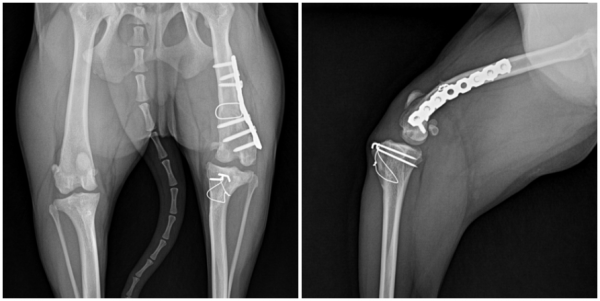

하쿠(가명)는 고랑성형술과 경골결절변위술·외측 연부조직 봉합술만으로는

교정이 충분하지 않았고 허벅지뼈가 안쪽으로 휘어진 변형까지 확인되어

이를 바로잡는 대퇴골 교정 절골술이 추가로 필요했습니다.

하쿠(가명)는 이미 여러 차례 수술을 받으면서

관절의 퇴행성 변화가 진행되었고

주변 인대와 연부조직도 함께 약해진 상태여서,

일반적인 경우보다 운동 제한 기간이 더 필요했고,

재활을 통해 근육량을 회복하고

관절을 지지하는 조직을 강화해야 했기 때문에

정기적인 재활운동이 반드시 필요했습니다.